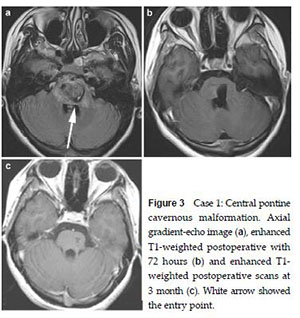

20170712151406 Figure 3 Case 1: Central pontine cavernous malformation. Axial gradient-echo image (a), enhanced T1-weighted postoperative with 72 hours (b) and enhanced T1- weighted postoperative scans at 3 month (c). White arrow showed the entry point.